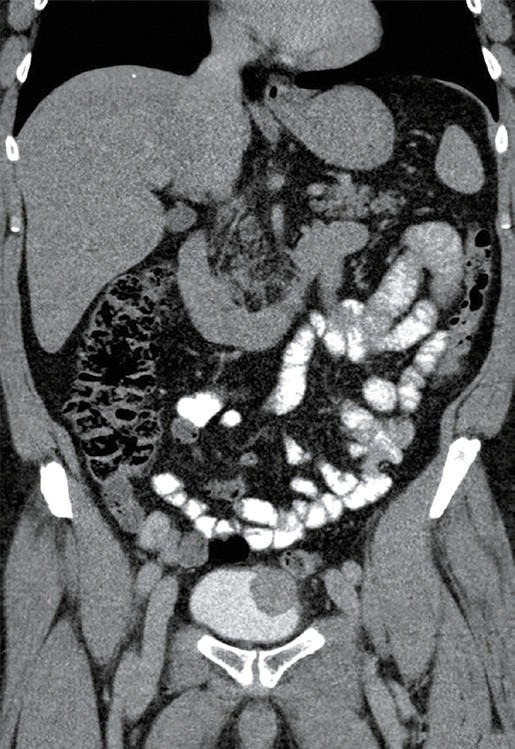

膀胱炎症性肌纤维母细胞瘤(IMTs)是罕见的,文献报道的病例数量有限。完全切除阴性切缘对于降低复发风险至关重要,同时保留膀胱功能对患者也至关重要。本研究描述了一名56岁的膀胱穹窿IMT患者,采用机器人辅助部分膀胱切除术,并辅以围手术期膀胱镜纹身来精确划定肿瘤边缘。手术首先使用黑眼染料在病变部位进行膀胱镜纹身,然后使用达芬奇Xi系统进行机器人切除。在保留膀胱容量的情况下,进行了完全的经壁切除和2层膀胱闭合。患者失血极少,术中无并发症,术后2天出院。随访检查,包括膀胱镜检查和计算机断层扫描,证实术后12个月无复发。膀胱镜纹身有助于术中肿瘤的明确定位,实现精确的切除和最小的膀胱壁损失。这种方法解决了机器人膀胱手术的一个关键挑战——在保持功能结果的同时缺乏触觉反馈。机器人辅助部分膀胱切除术与膀胱镜纹身是最大经尿道切除的一个有希望的替代方案,特别是在保留膀胱的三模治疗的背景下,对于那些不符合条件或不愿接受根治性膀胱切除术的患者。考虑到越来越多的人关注微创手术和全身治疗的进步,这项技术尤其重要。在未来,这种方法可以适用于输尿管机器人手术,以提高病灶定位。

Inflammatory myofibroblastic tumors (IMTs) of the bladder are rare, with a limited number of cases reported in the literature. Complete resection with negative margins is essential to reduce the risk of recurrence, while bladder function preservation is also crucial for the patient. This study describes a 56‑year‑old patient with a bladder dome IMT managed using robot‑assisted partial cystectomy facili‑ tated by perioperative cystoscopic tattooing to precisely demarcate the tumor margins. The procedure began with cystoscopic tattooing of the lesion using Black Eye dye, followed by robotic resection with the da Vinci Xi system. Complete transmural resection and a 2‑layer bladder closure were performed, with preservation of the bladder capacity. The patient experienced minimal blood loss, no intraopera‑ tive complications, and was discharged 2 days after the procedure. Follow‑up examinations, including cystoscopy and computed tomography, confirmed no recurrence 12 months after surgery. Cystoscopic tattooing facilitated clear intraoperative tumor localization, enabling precise resection and minimal bladder wall loss. This approach addressed a key challenge of robotic bladder surgery-lack of tactile feedback-while maintaining functional outcomes. Robot‑assisted partial cystectomy with cystoscopic tattooing represents a promising alternative to maximal transurethral resection, especially in the context of bladder‑sparing trimodal therapy, for patients who are not eligible for or unwilling to undergo radical cystectomy. This technique is particularly relevant given the increasing focus on minimally invasive procedures and advancements in systemic therapy. In the future, this method could be adapted for ureteral robotic surgeries to enhance lesion localization.